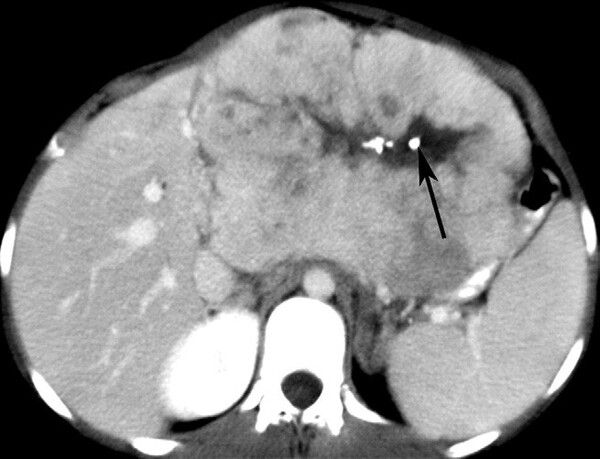

Hemangioma là u gan lành tính thường gặp nhất. Hemangioma thường gặp ở phụ nữ trẻ và 15-20% nhiều ổ. Mô học cho thấy một loạt các hồ máu và kênh mạch, các tổn thương lớn hơn tạo ra các vùng huyết khối và xơ. Siêu âm thấy một khối tăng âm, đồng nhất, giới hạn rõ, tăng âm phía sau yếu (Hình 1). Các tổn thương lớn hơn (>6cm) có thể không đồng nhất và giảm âm do huyết khối, hoại tử và thoái hóa nang. Các dấu hiệu CT cản quang gồm tăng quang dạng nốt ngoại vi ở thì động mạch với lấp đầy hướng tâm dần trong tổn thương ở thì tĩnh mạch cửa và thì muộn (hình 2). Vôi tĩnh mạch (phlebolith) có thể thấy trong tổn thương ở 15-20% trường hợp (Hình 2). MRI cho thấy tăng tín hiệu trung bình trên T2W, thường ít hơn so với nang đơn thuần, tín hiệu thấp trên T1W. MRI sau tiêm thuốc cho thấy bắt thuốc dạng nốt gián đoạn phía ngoại vi ở thì động mạch, đó là đặc điểm điển hình của hemangioma (Hình 3). MRI thì tĩnh mạch và thì muộn có thể thấy các nốt bắt thuốc lớn dần và hợp lưu với lấp dầy trung tâm ở các mức độ khác nhau tương tự như CT.

Hình 2. Bệnh nhân nữ 42 tuổi, hemnagioma. CT không cản quang (A) thấy đốm đóng vôi (mũi tên) ở ngoại vi khối giảm đậm độ gợi ý vôi tĩnh mạch. Có tăng quang dạng nốt ngoại vi (mũi tên ) ở thì động mạch (B), lấp vào trung tâm (mũi tên) ở thì tĩnh mạch cửa (C). Thì muộn (D) thấy lấp vào một phần tổn thương (mũi tên) do huyết khối.